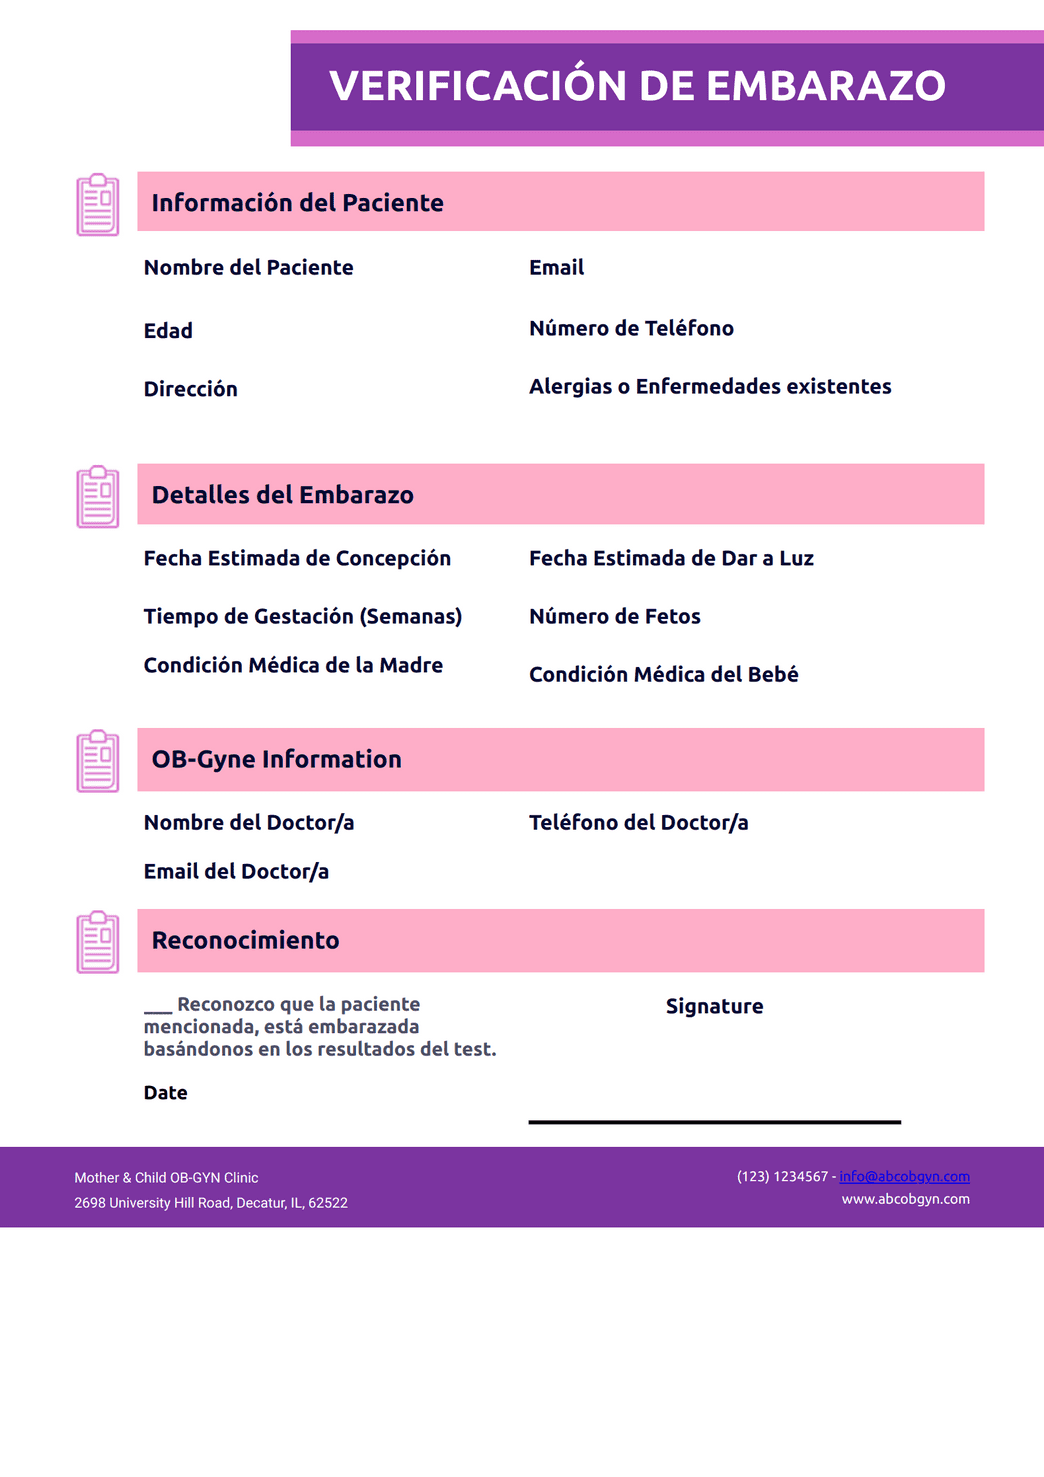

Prueba de embarazo escrita on sale, Verificacion de Embarazo Plantilla Plantillas PDF Jotform on sale

Verificacion de Embarazo Plantilla Plantillas PDF Jotform